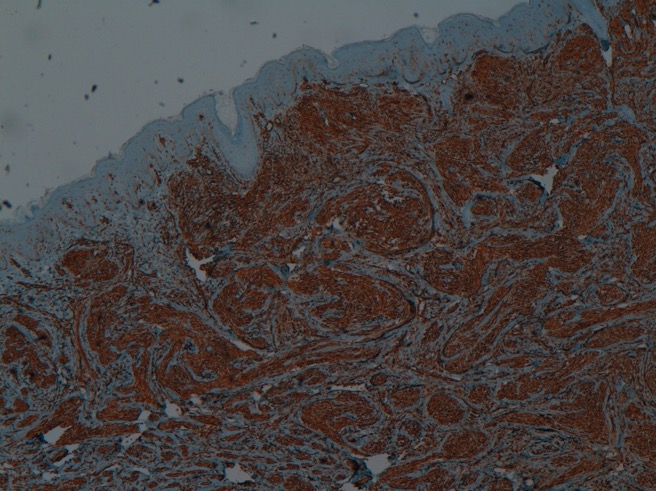

Neurothekeoma is a rare benign neoplasm of uncertain histogenesis. Progresses in immunohistochemistry have brought new insights into its cellular differentiation and origin, recognizing the possibility of a fibrohystiocitic lineage. Also, it has been subclassified histopathologically as either myxoid, cellular, or mixed type, depending on the amount of myxoid matrix and on immunohistochemical analysis. Few cases of cellular neurothekeoma have been reported. Most of them are found on the head, neck and upper extremities and mostly in young female adults. On review of literature we have not found reports regarding dermoscopic features of neurothekeoma. Herein we report an uncommon case of cellular neurothekeoma on the axilla of a 7–year-old girl, with description of its dermoscopic findings.

Hornick JL, Fletcher CD. Cellular neurothekeoma: detailed characterization in a series of 133 cases. Am J Surg Pathol. 2007;31:329-40.

Fetsch JF, Laskin WB, Hallman JR. Neurothekeoma: an analysis of 178 tumors with detailed immunohistochemical data and long-term patient follow-up information. Am J Surg Pathol. 2007;31:1103-14.

Jaffer S, Ambrosini-Spaltro A, Mancini AM, Eusebi V, Rosai J. Neurothekeoma and plexiform fibrohistiocytic tumor: mere histologic resemblance or histogenetic relationship? Am J Surg Pathol. 2009; 33: 905-13.

Barnhill RL, Dickersin GR, Nickeleit V, Bhan AK, Muhlbauer JE, Phillips ME, et al. Studies on the cellular origin of neurothekeoma: clinical, light microscopic, immunohistochemical, and ultrastructural observations. J Am Acad Dermatol. 1991;25:80-8.

Calonje E, Wilson-Jones E, Smith NP, Fletcher CD. Cellular 'neurothekeoma': an epithelioid variant of pilar leiomyoma? Morphological and immunohistochemical analysis of a series. Histopathology. 1992;20:397-404.

Misago N, Satoh T, Narisawa Y. Cellular neurothekeoma with histiocytic differentiation. J Cutan Pathol. 2003; 30:196-201.

Wang GY, Nazarian RM, Zhao L, Hristov AC, Patel RM, Fullen DR, et al. Protein gene product 9.5 (PGP9.5) expression in benign cutaneous mesenchymal, histiocytic, and melanocytic lesions: comparison with cellular neurothekeoma. Pathology. 2017; 49 :44-9.

Plaza JÁ Torres-Cabala C, Evans H, Diwan AH Prieto VG. Immunohistochemical expression of S100A6 in cellular neurothekeoma: clinicopathologic and immunohistochemical analysis of 31 cases. Am J Dermatopathol. 2009; 31: 419-22